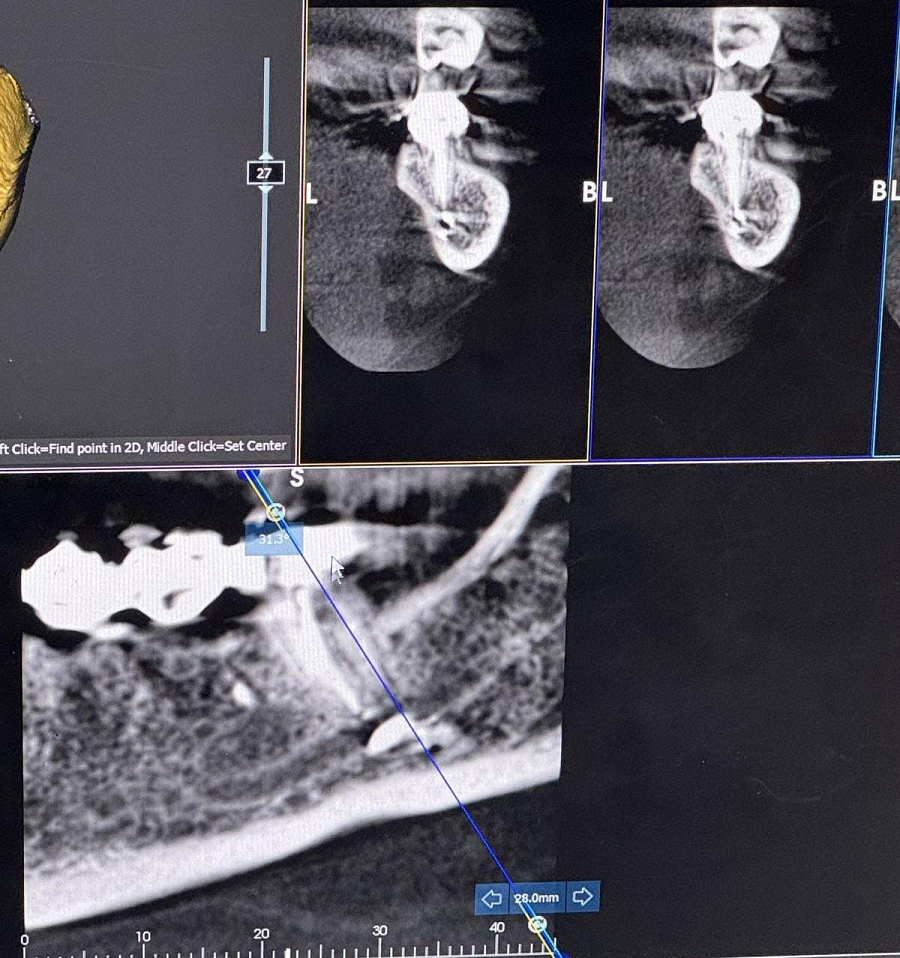

Hadisədən dərhal sonra üzümdə və dodaqlarımda hissiyyatsızlıq yarandı. Buna baxmayaraq, həkim vəziyyəti ciddiyə almaraq “yod çək, keçəcək” deyib, məni evə göndərdi. Bundan sonra vəziyyətim sürətlə pisləşdi. Digər tibb müəssisəsində təcili əməliyyat edərək həmin zərərli maddəni orqanizmdən xaric etdilər. Bir gün geciksəydim, sinir toxumamda daimi iflic riski yaranacaqdı. Hazırda üzümdə hissiyyat hələ tam bərpa olunmayıb, bunun uzun müddət davam edəcəyi bildirilib”.

R.Zaxarova bununla bağlı Səhiyyə Nazirliyinə müraciət etdiyini, lakin özəl müəssisə olduğu üçün məsələyə laqeyd yanaşıldığını deyib: “Bütün bu müddət ərzində məsuliyyət daşıyan tərəf mənə heç bir köməklik göstərmədi. Həkim məni başqa bir həkimə yönləndirəcəyini dedi, lakin onu da etmədi. Əlimdə rentgen görüntüləri və əməliyyat sənədləri var”.